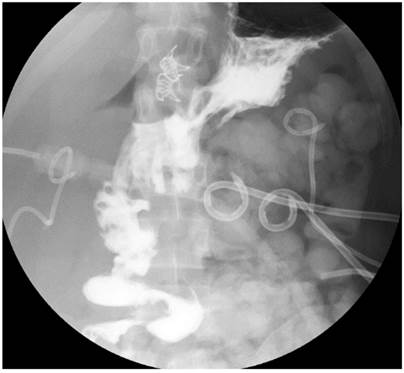

Durante el posoperatorio se realizó como seguimiento una radiografía de vías digestivas que confirmó la no continuidad pilórica con adecuada permeabilidad de la gastroyeyunoanastomosis, y una tomografía abdominal contrastada que mostró una disminución de la colección intraabdominal sin extravasaciones del medio de contraste.

A gastrointestinal tract X-ray was performed as a follow-up during the postoperative stage, showing no pyloric continuity with adequate patency of the gastrojejunostomy. In addition, a contrasted abdominal CT scan showed a decrease in the intra-abdominal collection without extravasation of the contrast medium.

Al quinto día posterior al procedimiento endoscópico se realizó como seguimiento imagenológico una radiografía de vías digestivas que confirmó la no continuidad pilórica con adecuada permeabilidad de la gastroyeyunoanastomosis y tomografía abdominal contrastada que mostró una disminución de la colección intraabdominal sin extravasación del medio de contraste (Figuras 4 y 5).

Figura 4 Radiografía de vías digestivas que muestra exclusión pilórica con adecuado paso de contraste por la gastroyeyunoanastomosis.